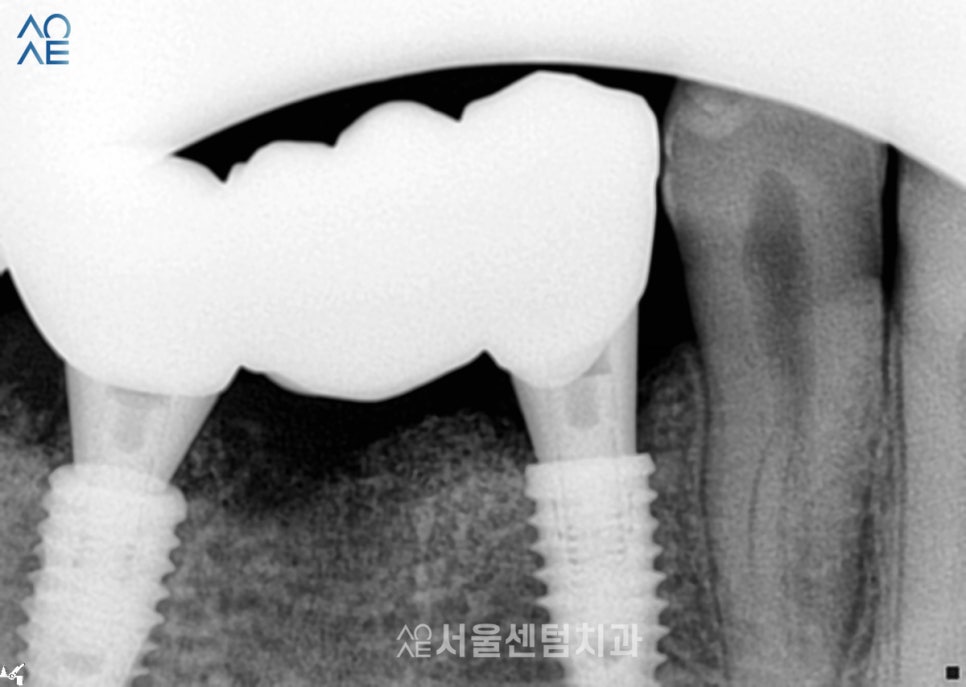

20대임플란트 완성

왼쪽(사진상 오른쪽)에도 깨진 치아가 있어서

함께 치료를 권유 드렸지만

환자분의 일정 상의 이유로 잠시 보류되었습니다.

대신 추가적으로 상담을 해드려서

나중에 준비가 되실 때

진행을 하기로 했습니다.

그래도 다른 치료들은 모두

무사히 마칠 수 있었습니다.

특히 앞니가 심미적으로 많이 개선되어

마음에 들어하셨습니다.

성공적인 20대임플란트 결과

치아의 머리가 부러져서 치아의 뿌리만 남은 경우는

연령대 구분 없이 많이 볼 수 있는데요.

이 분의 경우엔 오래 방치하지 않고

빠른 시일내에 치과에 방문해주셔서

염증이나 다른 문제가 없었습니다.